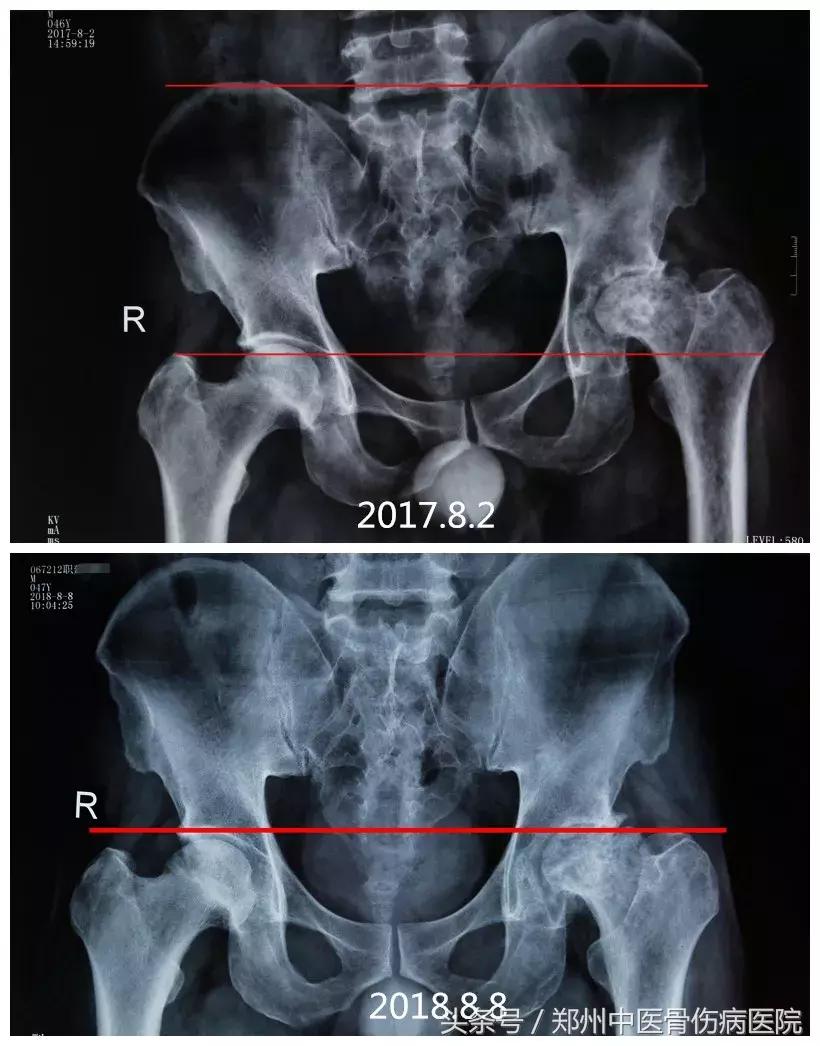

下图为患者职某片子对比图:

2017年8月2日治疗前,骨盆倾斜严重,导致双下肢不等长,走路严重跛行;2018年8月8日,经治疗后,已基本恢复正常,大大提高了生活质量。

2018年8月8日片子显示,左侧股骨头骨小梁清晰,骨密度均匀,出现间隙。